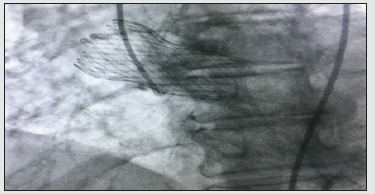

Shared decision-making was performed with the patient and eventually a diagnostic right and left coronary angiography with possible interventions was agreed upon to evaluate her vessels. A pre-procedural computed tomography scan of the chest was obtained to visualize the location of the valve prosthetic. The right femoral artery was directly entered, and a 6-French sheath was placed. The coronary angiography was performed via a 6-French Judkins technique, which showed a totally occluded proximal right coronary artery (Figure 1). Therefore, a JR4 guide catheter was advanced and engaged the obstruction. After administering intravenous heparin, a CHOICE floppy wire was advanced across the total occlusion and a 2.5 mm x 8 mm balloon was serially deployed to achieve patency (Figure 2). Angiography was then performed with a 2.75 mm x 24 mm drug-eluting stent to achieve a peak pressure of 14 atmospheres (Figure 3). Femoral angiography was then performed, and an Angio-Seal device was placed. A cine fluoroscopy confirmed the correct positioning of the metallic stent. Post-intervention angiography showed a distal TIMI grade 3 flow, but no residual stenosis or evidence of distal embolization was noted. The patient was started on dual antiplatelet therapy of aspirin and clopidogrel. The patient’s initial symptoms resolved within two days after the procedure and were discharged home on day three of hospitalization. She was instructed to continue taking dual antiplatelet therapy along with her other medications. Followup visits were scheduled with her primary care physician at two weeks and cardiologist at one month, which were unremarkable.

Figure 1: Coronary angiography showing total occlusion of the right coronary artery